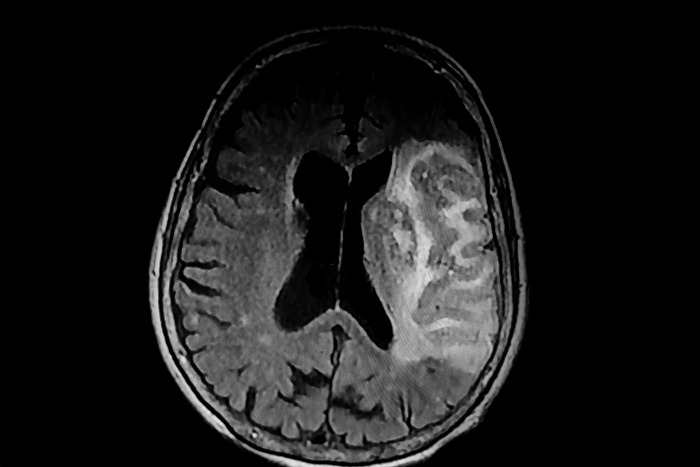

img_20241025145120_4cbb8590.jpg 기사의 이해를 돕기 위한 사진 / Douglas Olivares-Shutterstock.com

뇌출혈이란 두개 내에 출혈이 있어 생기는 모든 변화를 말하는 것으로 출혈성 뇌졸중이라고도 한다.

뇌출혈은 여러 가지 방법으로 구분하고 있으나 크게 외상에 의한 출혈과 자발성 출혈로 구분할 수 있다.

외상에 의한 출혈은 급성 경막하 출혈, 만성 경막하 출혈, 경막외 출혈 등 두부 외상과 직간접적으로 연관이 있는 출혈을 말한다. 자발성 뇌출혈이란 다음과 같은 질환 중에 뇌출혈을 일으킨 것을 말한다.

고혈압성 뇌출혈은 만성 고혈압과 관련 있는 경우가 많으며, 혈압 상승의 정도 및 기간과 관련이 있다. 또 고혈압성 뇌출혈은 출혈 부위에 따라 피각 출혈, 시상 출혈, 피질하 출혈, 뇌교 출혈, 소뇌 출혈로 나눌 수 있다.

고혈압성 뇌출혈은 뇌졸중 가운데 약 10%를 차지하며 나이, 고혈압, 뇌경색, 관상동맥 질환, 당뇨 등이 그 위험인자로 알려져 있다. 대부분 50대에서 60대에 주로 발생하며 성별의 차이는 거의 없다. 고혈압성 뇌출혈은 뇌내출혈을 초래하여 약 40% 정도의 사망률을 보인다.

뇌동맥류에 의한 출혈은 90% 정도가 뇌주막하 출혈로 발생하며, 사람이 일생에서 가장 극심한 두통을 호소하는 것으로 알려져 있다.